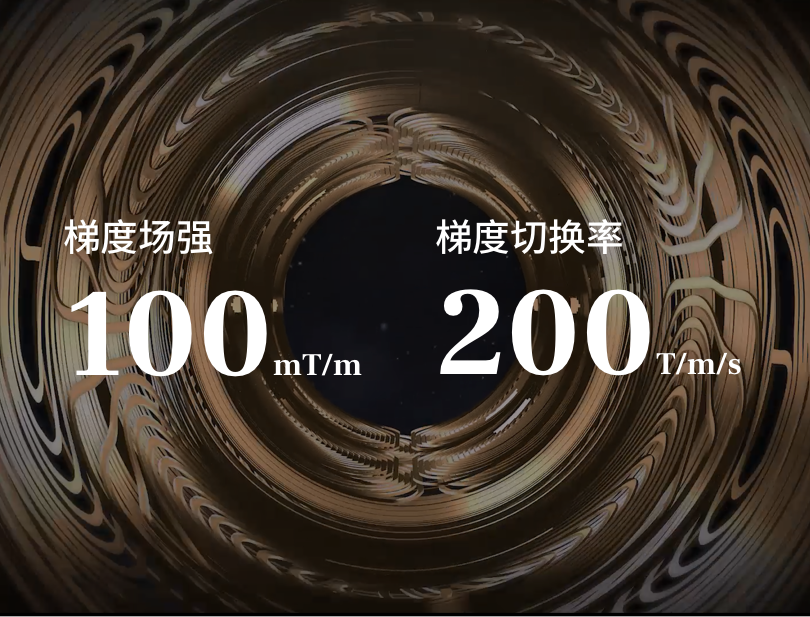

uMR 790 探索3.0T磁共振所具有的高性能探索磁体和探索梯度,是科研型磁共振区别于临床型磁共振重要的硬件基础。

探索梯度

突破高强度、高线性度及高精度梯度线圈设计及制造工艺瓶颈,铸就超强劲梯度「引擎」。